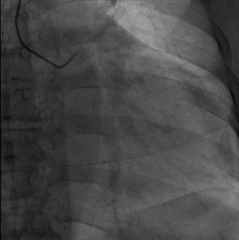

手术经过:首先冠脉造影延迟显影可见冠状窦开口及靶静脉大致走行

AP

LAO45